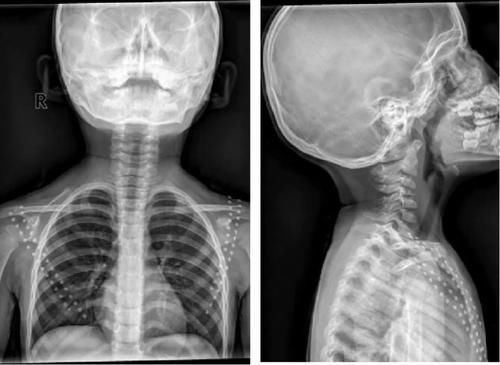

Case13:F,4y;腰痛1月余,加重半月。